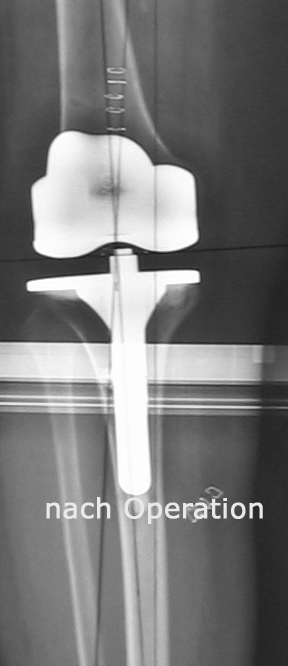

Knieprothese

Welcher Typ einer Knieprothese für die Behandlung der Kniegelenksarthrose verwendet wird hängt neben dem Patientenalter vorwiegend davon ab, welche Teile des Gelenks abgenützt sind. So können bei isolierten Abnützungen des inneren Gelenksteils sogenannte Schlittenprothesen ( linkes Bild) und bei Abnützungen des gesamten Gelenks Totalprothesen  (mittleres Bild) eingesetzt werden: In besonders schweren Fällen von Fehlstellung in Kombination mit fehlender oder unzureichender Bandstabilität werden auch immer wieder sogenannte achsegeführte oder gekoppelte Prothesenmodelle (rechtes Bild) eingesetzt.